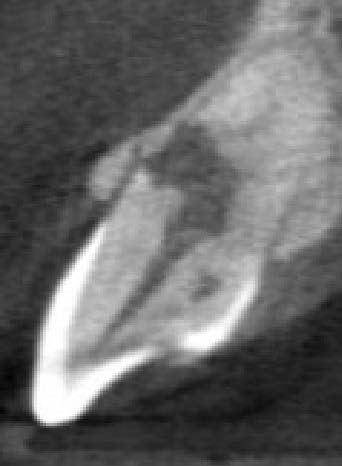

The CBCT revealed intraroot perforating resorption on the vestibular root surface. In addition, a possible cause of resorption was identified as Oehlers' Type I invagination (1957), which was based on the radiological findings. According to the classification, Type I invagination is covered with enamel and is located within the coronal part, extending no further than the enamel-dentin junction. The authors believe that the infected invagination zone with subsequent creeping infection of the root pulp brought about the resorption. The response to the cold stimulus was very insignificant, especially in comparison with tooth 12. This made it clear that an irreversible destructive process is going on in the damaged tooth. Since the patient was planning orthodontic treatment and the resorption process could grow worse, it was decided to conduct endodontic treatment.

In favor of external resorption was the shape of the defect, with the wider defect facing the bone, the shape of the defect was not rounded, which would be characteristic of internal resorption.

Also, there were signs in favor of internal resorption. The defect was below the cervical part, which is not typical of external cervical resorption. The response to cold stimuli reduced, which is not characteristic of external resorption, as it affects the pulp only in the last stages of tooth structures decay. Furthermore, the X-ray obliteration of the root canal beyond the resorption area is not characteristic of external resorption. Visit 1: Pre-op X-ray plus anesthesia with sol. Ubisthesini 4% -1 ml, isolation with rubberdam. The access was made as close as possible to the incisal edge. When opened, at first glance the pulp chamber looked quite II.